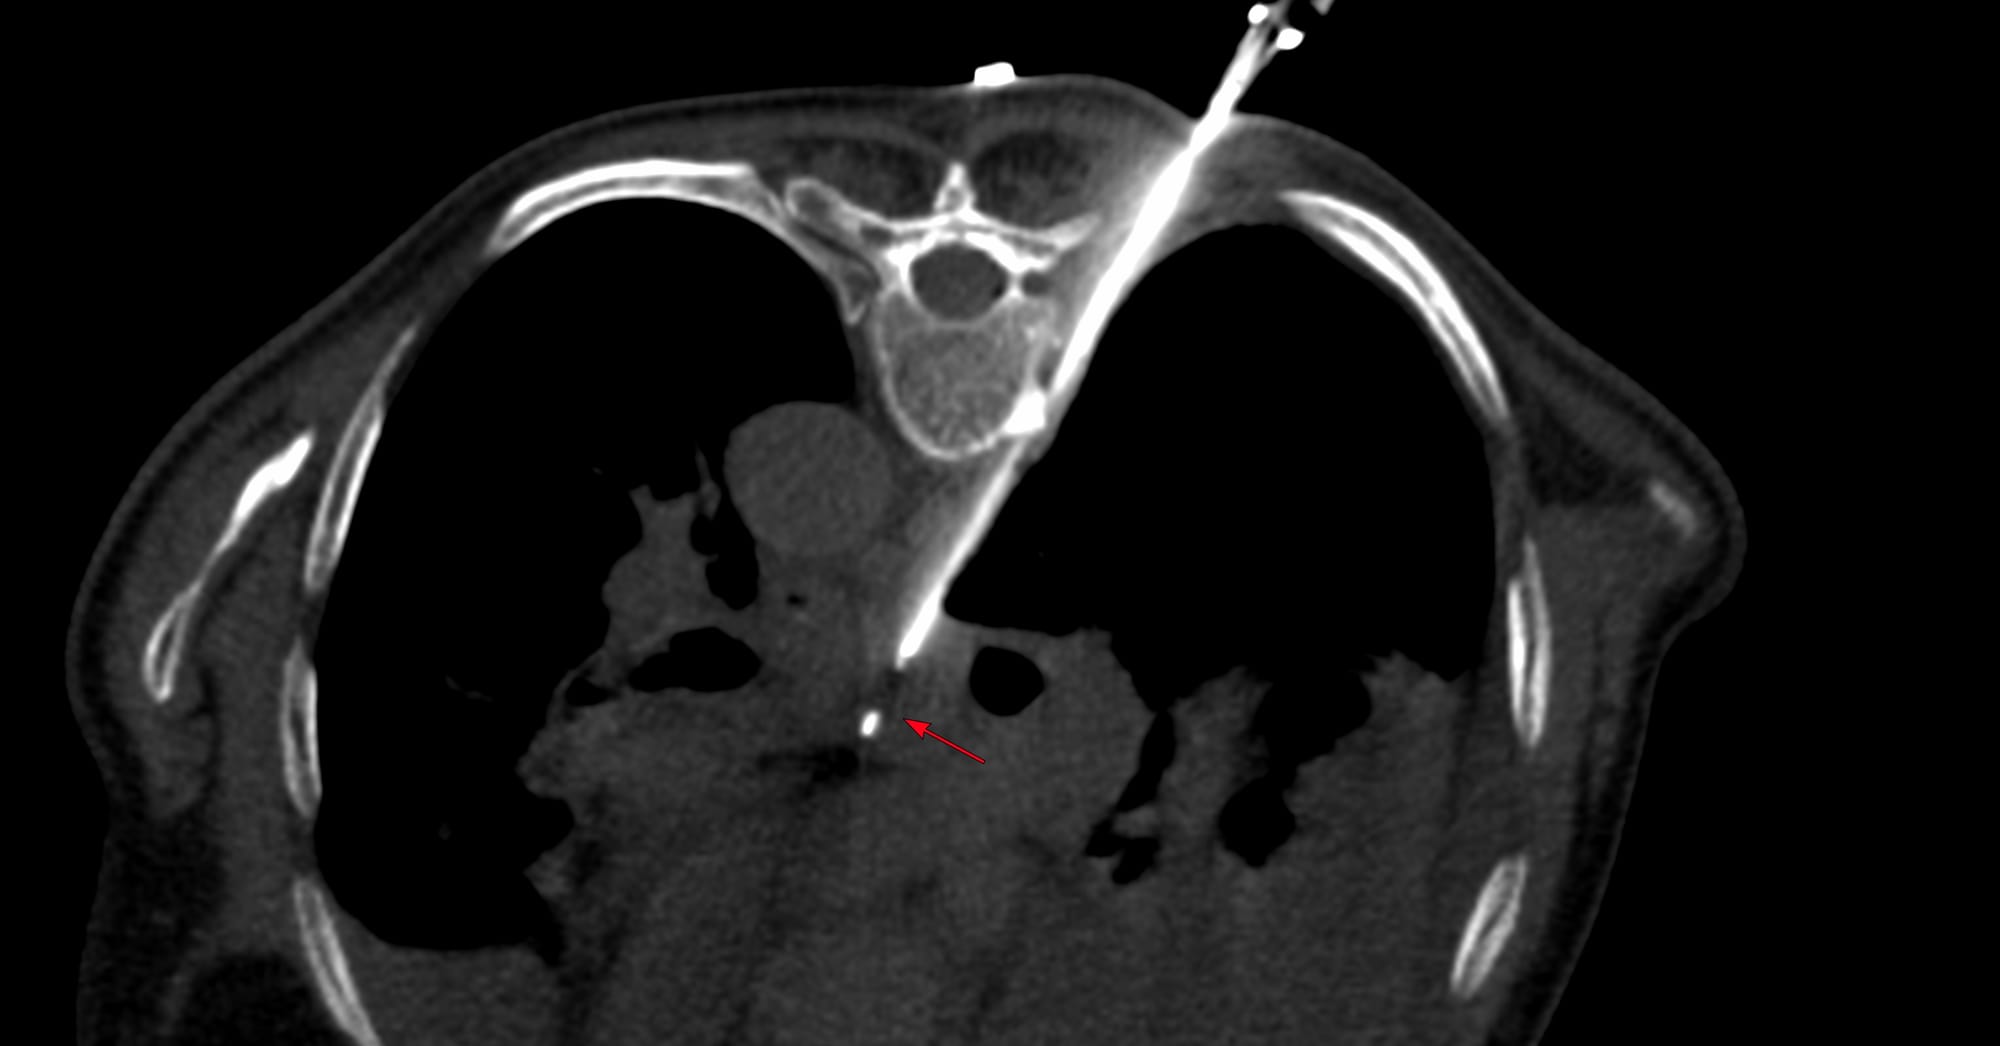

COD 127 - Maxillary Sinus Biopsy